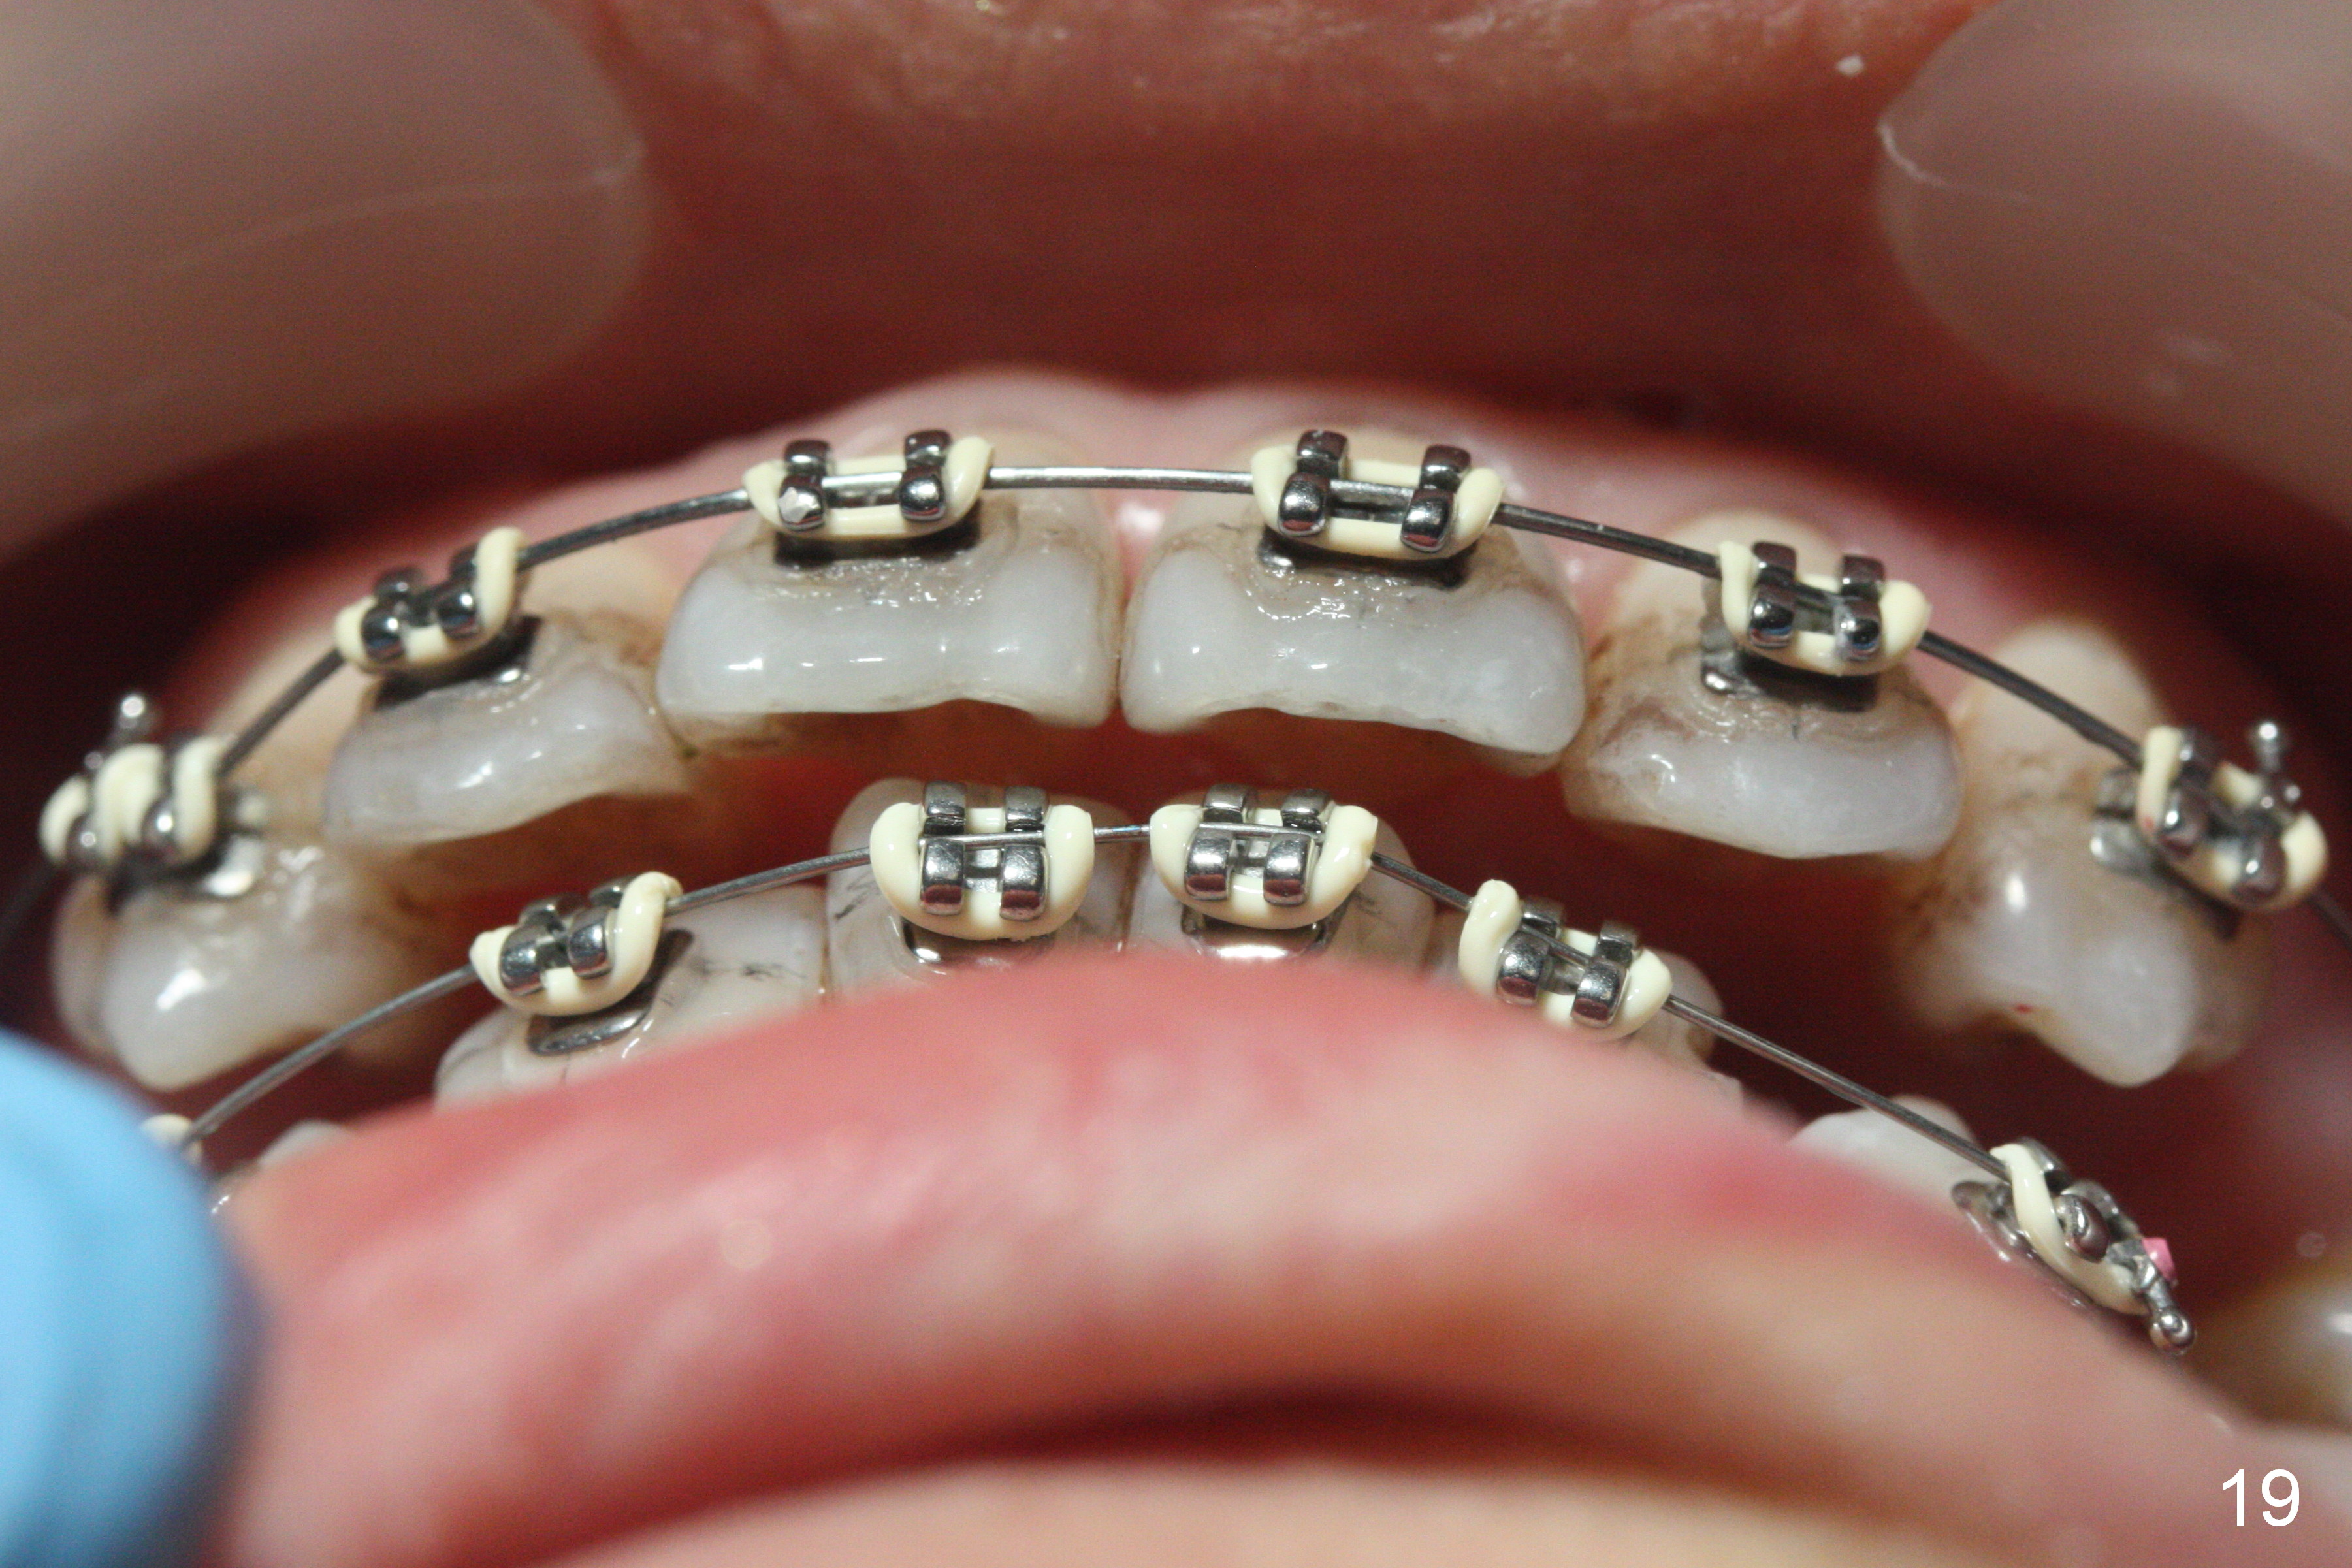

Fig.15-17 are taken nearly 2 months post banding. The upper 16 niti is still not fully engaged. Two weeks later, lower brackets are placed with 12 niti wire and occlusal composite (Fig.18-20). Overjet is excessive (Fig.19). Consider distalizing the upper anterior teeth when the upper arch wire changes to a rectangular one.